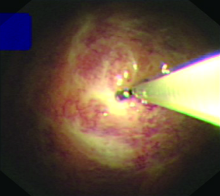

Objective: To evaluate the diagnostic value of cryobiopsy in patients with suspected tuberculous pleurisy by comparing cryobiopsy and biopsy forceps biopsy. Methods: A prospective study was conducted. A total of 73 patients with suspected tuberculous pleurisy were consecutively included in Harbin Chest Hospital from May 2022 to August 2024 in accordance with the enrollment criteria. All enrolled patients underwent internal medicine thoracoscopic biopsy forceps biopsy and cryobiopsy simultaneously. Both the biopsy tissue and pleural effusion were tested by GeneXpert MTB/RIF, Mycobacterium tuberculosis resistance gene-on-chip method (referred to as “drug resistance gene-on-chip method”), and Mycobacterium tuberculosis BACTEC MGIT 960 (referred to as “MGIT 960”) culture and pathological examination. Based on the final clinical diagnosis results, the differences in tissue specimen diameter, pathological positive rate, etiological positive rate, complications and other indicators of biopsy forceps biopsy and cryobiopsy were compared, and the diagnostic value of internal thoracoscopic cryobiopsy for patients with suspected tuberculous pleurisy was evaluated. Results: All 73 patients obtained a definitive diagnosis. Among them, 64 patients (87.7%, 64/73) achieved a definitive diagnosis by biopsy forceps biopsy, while 71 patients (97.3%, 71/73) did so by cryobiopsy. A total of 60 cases (82.2%, 60/73) were diagnosed with tuberculous pleurisy, including 43 cases (58.9%, 43/73) of drug sensitive tuberculous pleurisy and 17 cases (23.3%, 17/73) of drug-resistant tuberculous pleurisy (including 3 cases of monodrug-resistant, 8 cases of multidrug-resistant, 1 case of polydrug-resistant, 2 cases of pre-extensively drug-resistant, and 3 cases of extensively drug-resistant). The remaining 13 cases (17.8%, 13/73) were diagnosed with pleural effusion due to other causes, including 6 cases (8.2%, 6/73) of malignant pleural mesothelioma, 2 cases (2.7%, 2/73) of adenocarcinoma, 1 case (1.4%, 1/73) of squamous cell carcinoma, 1 case (1.4%, 1/73) of small cell neuroendocrine carcinoma, 2 cases (2.7%, 2/73) of inflammation, and 1 case (1.4%, 1/73) of amyloidosis. The diameter of the tissue specimen of cryobiopsy ((7.47±0.71) mm) was significantly larger than that of biopsy forceps biopsy ((2.34±0.22) mm), and the histopathological positivity rate of cryobiopsy (97.3%, 71/73) was significantly higher than that of biopsy forceps biopsy (87.7%, 64/73); the differences were statistically significant (t=58.820, P<0.001; χ2=4.818, P=0.028). The histopathogenic positivity rate of cryobiopsy (GeneXpert MTB/RIF: 91.7%, 55/60; resistance gene chip examination: 61.7%, 37/60; MGIT 960 culture: 73.3%, 44/60) was significantly higher than those of biopsy clamp biopsy (GeneXpert MTB/RIF was 70.0% (42/60), drug resistance gene microarray was 28.3% (17/60), MGIT 960 culture was 40.0% (24/60)), and the differences were statistically significant (χ2=8.015, P=0.005; χ2=13.470, P<0.001; χ2=13.570, P<0.001). The diagnostic sensitivity of cryobiopsy for tuberculosis pleurisy (98.5%, 66/67) was significantly higher than that of biopsy forceps biopsy (88.9%, 56/63), and the difference was statistically significant (χ2=5.202, P=0.023). No serious adverse reactions occurred postoperatively in either biopsy methods. A total of 16 cases (21.9%, 16/73) developed mild chest pain, among which the incidence of chest pain in cryobiopsy (5.5% (4/73)) was lower than that in biopsy (16.4%, 12/73), and the difference was statistically significant (χ2=4.492, P=0.034). Conclusion: Internal thoracoscopic cryobiopsy has high diagnostic sensitivity and the advantage of high safety for patients with suspected tuberculous pleurisy, and can further improve the precise treatment level of tuberculous pleurisy through drug susceptibility testing.